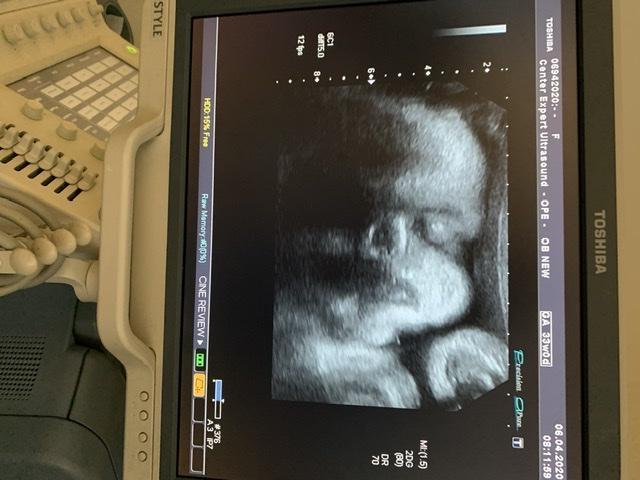

33 недели и прогноз на крупный плод 🙄🙄..

Вес плода на 33 недели 2413... сказала ог на 35 недель и че я себе думаю, как я собираюсь рожать, если ребёнок уже опережает на 2 недели срок.. 😭😭

Ну и фоточки) наши первые, малыш повернулся впервые ❤️❤️